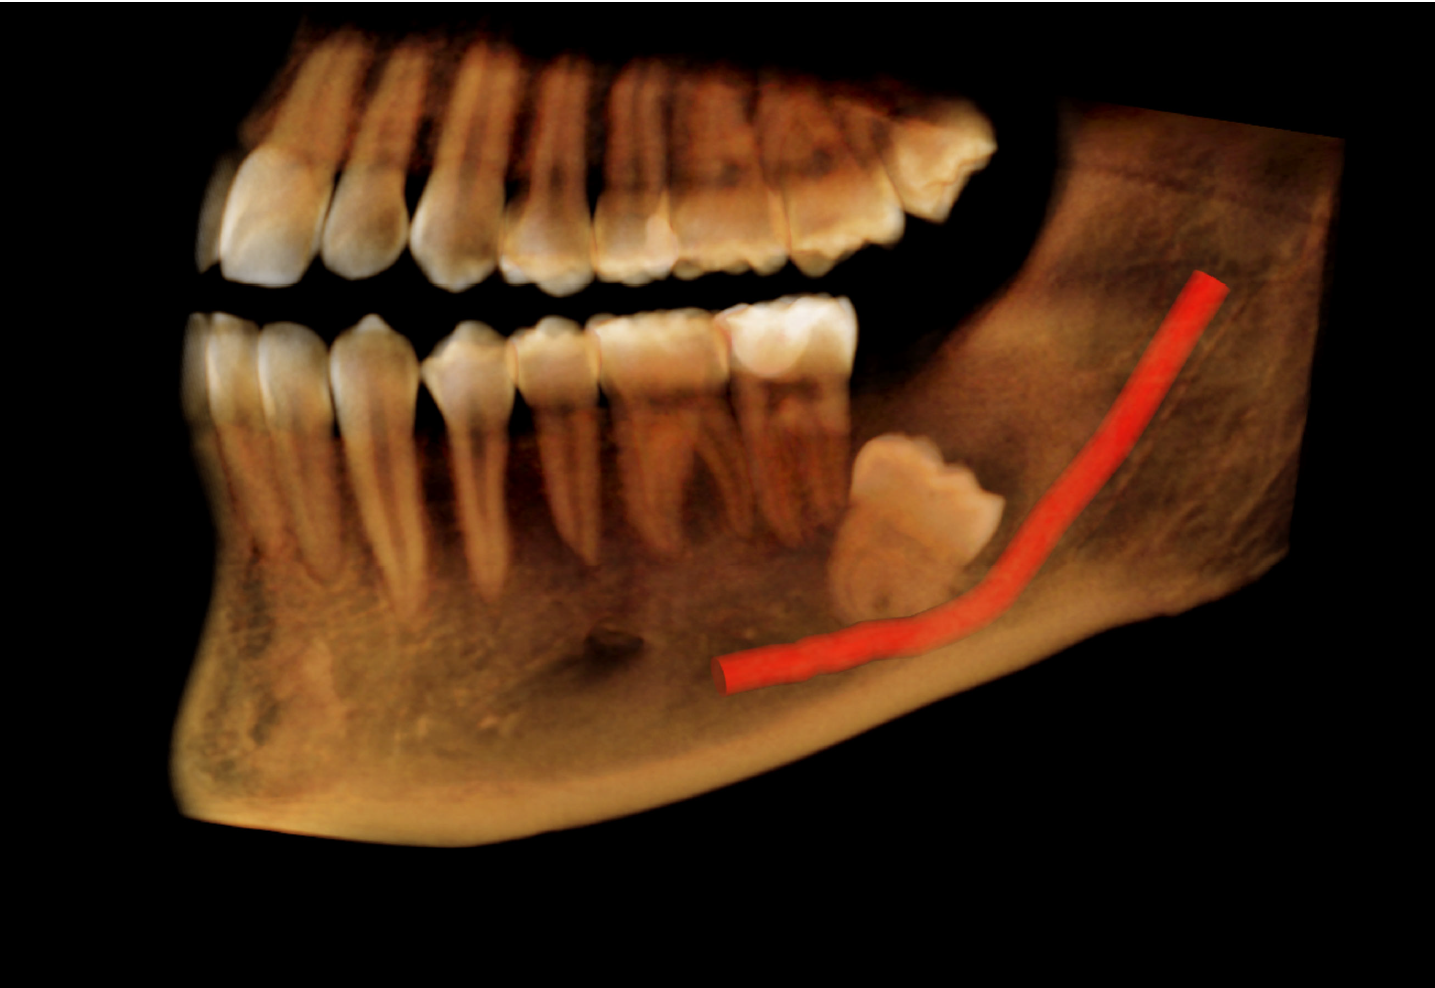

Nerve canal tracing on Cone Beam CT Image